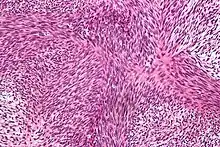

| Micrograph of malignant peripheral nerve sheath tumour with the typical herringbone pattern. H&E stain. | |